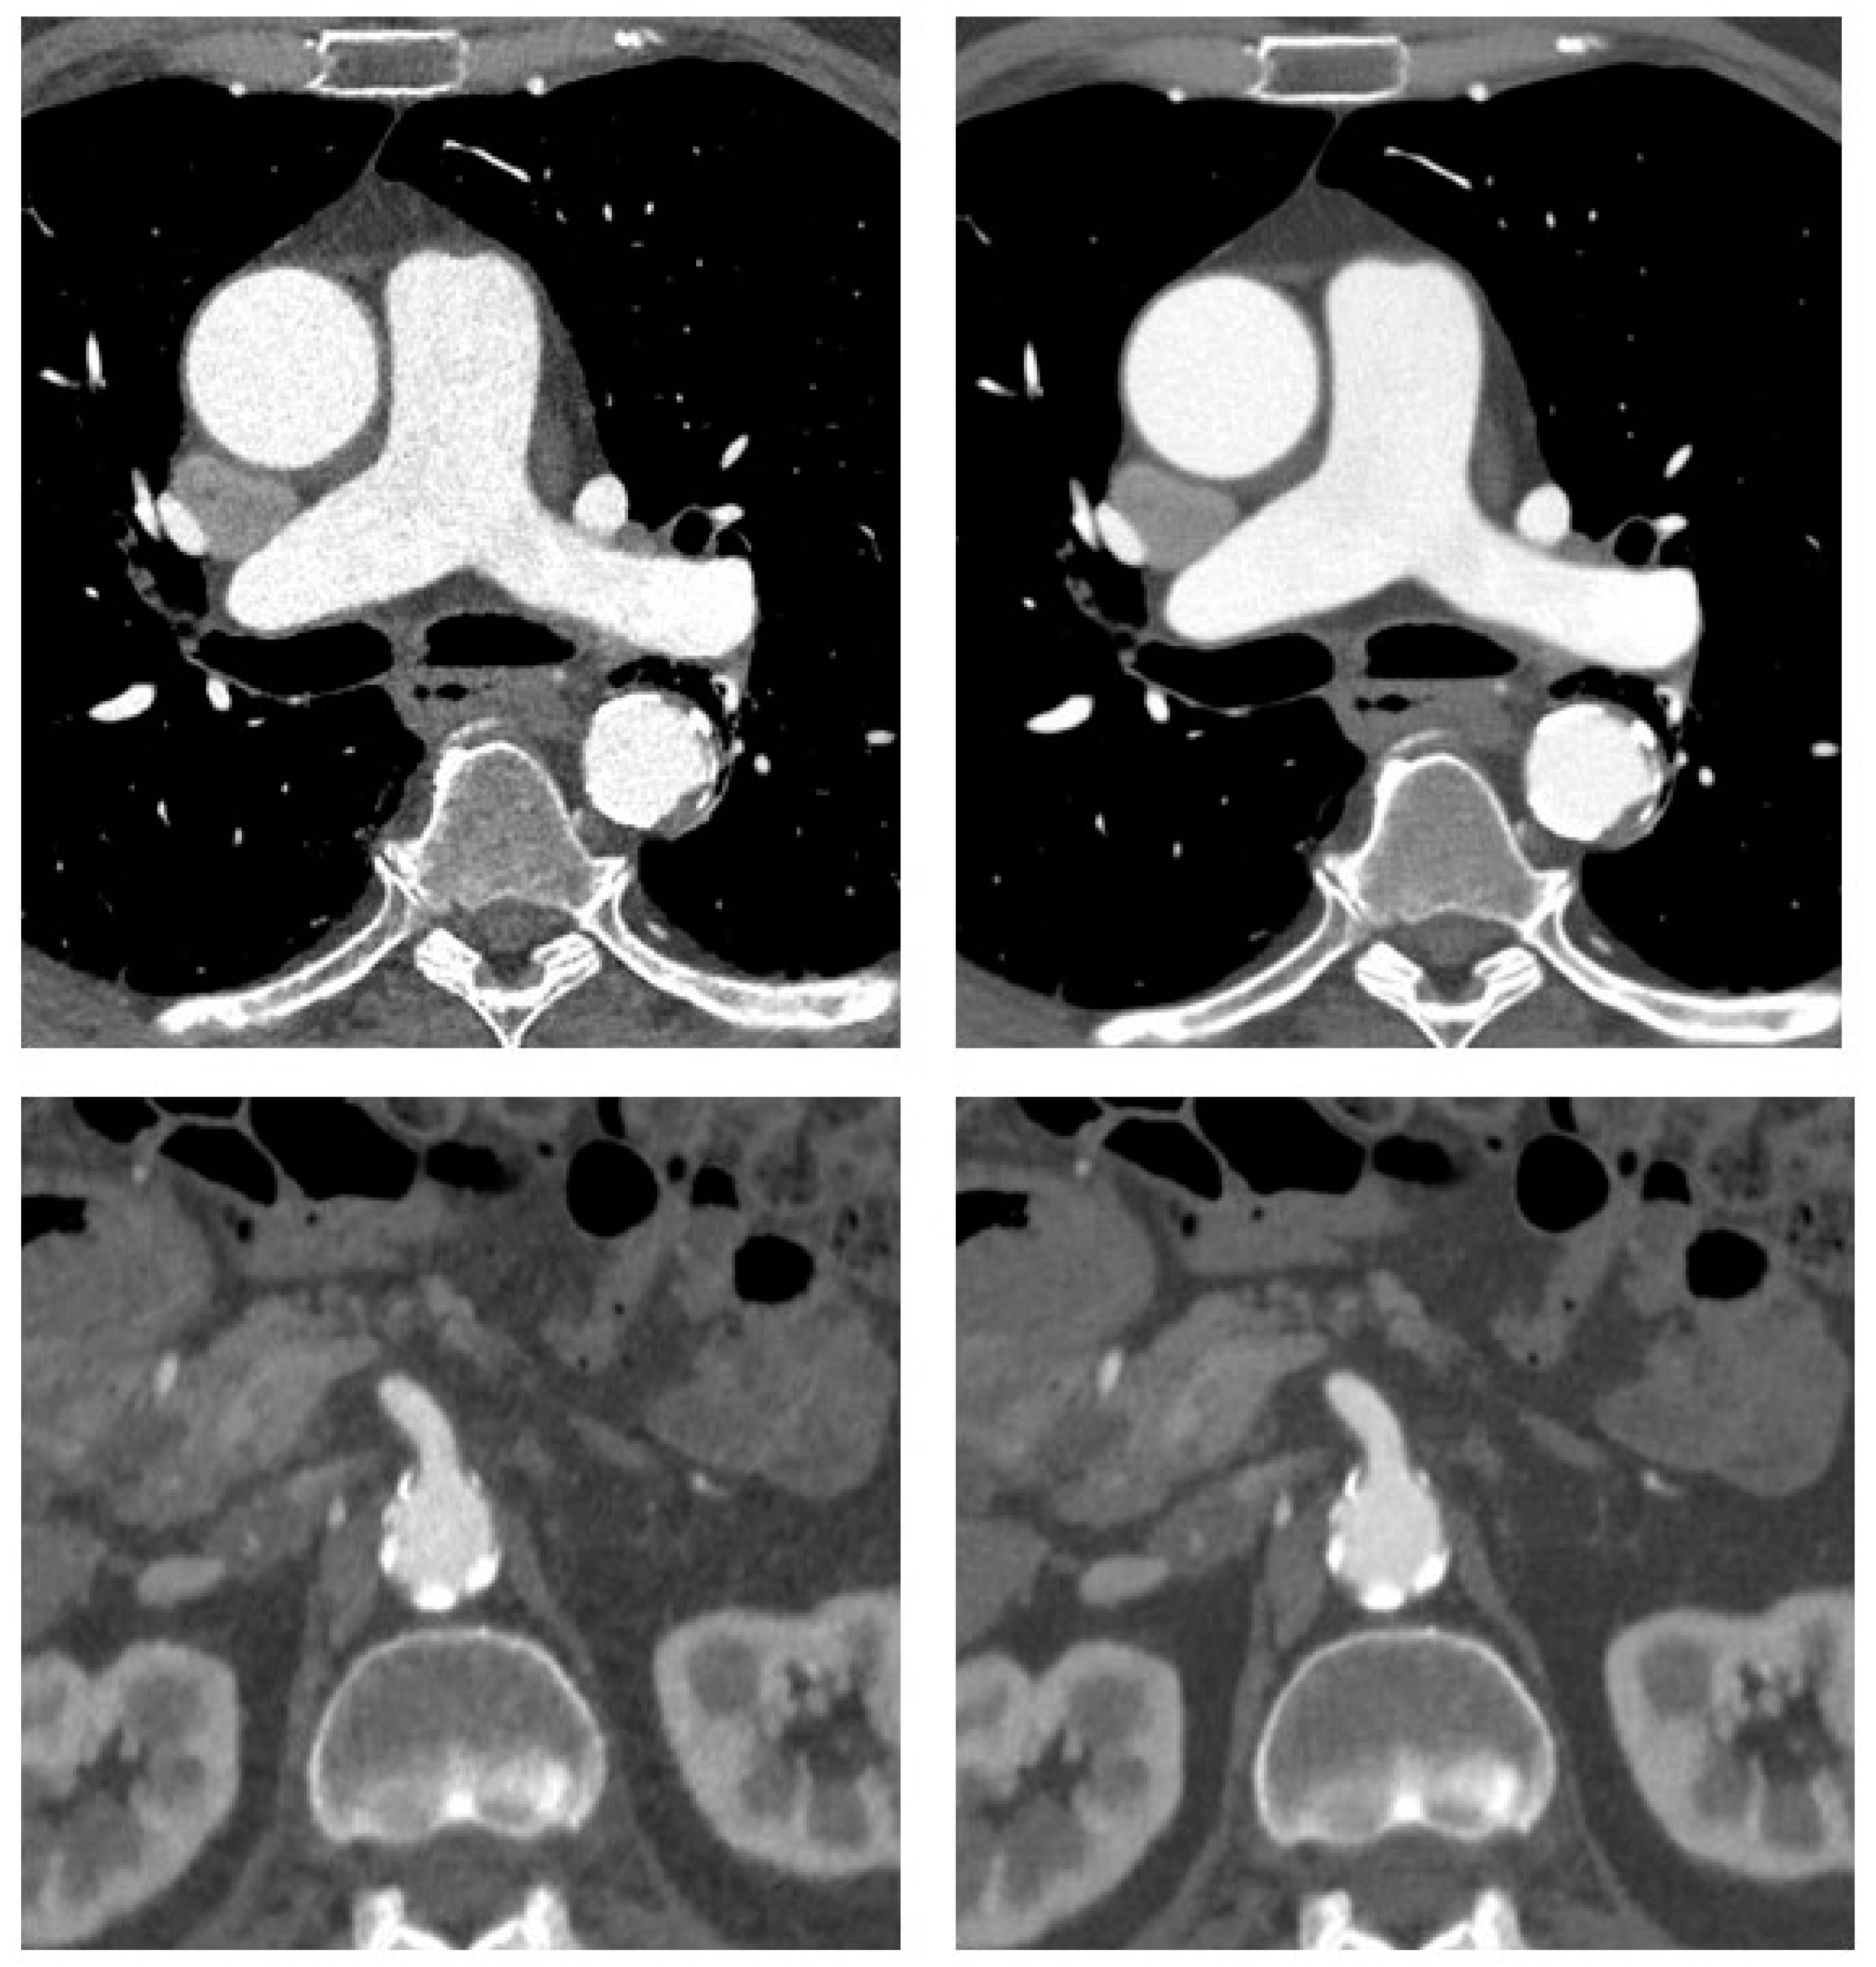

| Obese Patients (n = 17) | Normal-Weight Patients (n = 17) | |||||

|---|---|---|---|---|---|---|

| Contrast-to-Noise-Ratio | ASIR-V | DLIR | p-Value | ASIR-V | DLIR | p-Value |

| Ascending Aorta | 7 (6–8) | 14 (12–16) | <0.0001 | 8 (8–9) | 19 (15–22) | <0.0001 |

| Thoracic descending aorta | 7 (6–7) | 13 (11–15) | <0.0001 | 8 (7–9) | 18 (13–19) | <0.0001 |

| Abdominal aorta | 12 (8–13) | 19 (15–24) | <0.0001 | 9 (7–12) | 16 (11–21) | <0.0001 |

| Iliac arteries | 14 (12–15) | 21 (19–25) | <0.0001 | 15 (13–16) | 24 (19–28) | 0.001 |